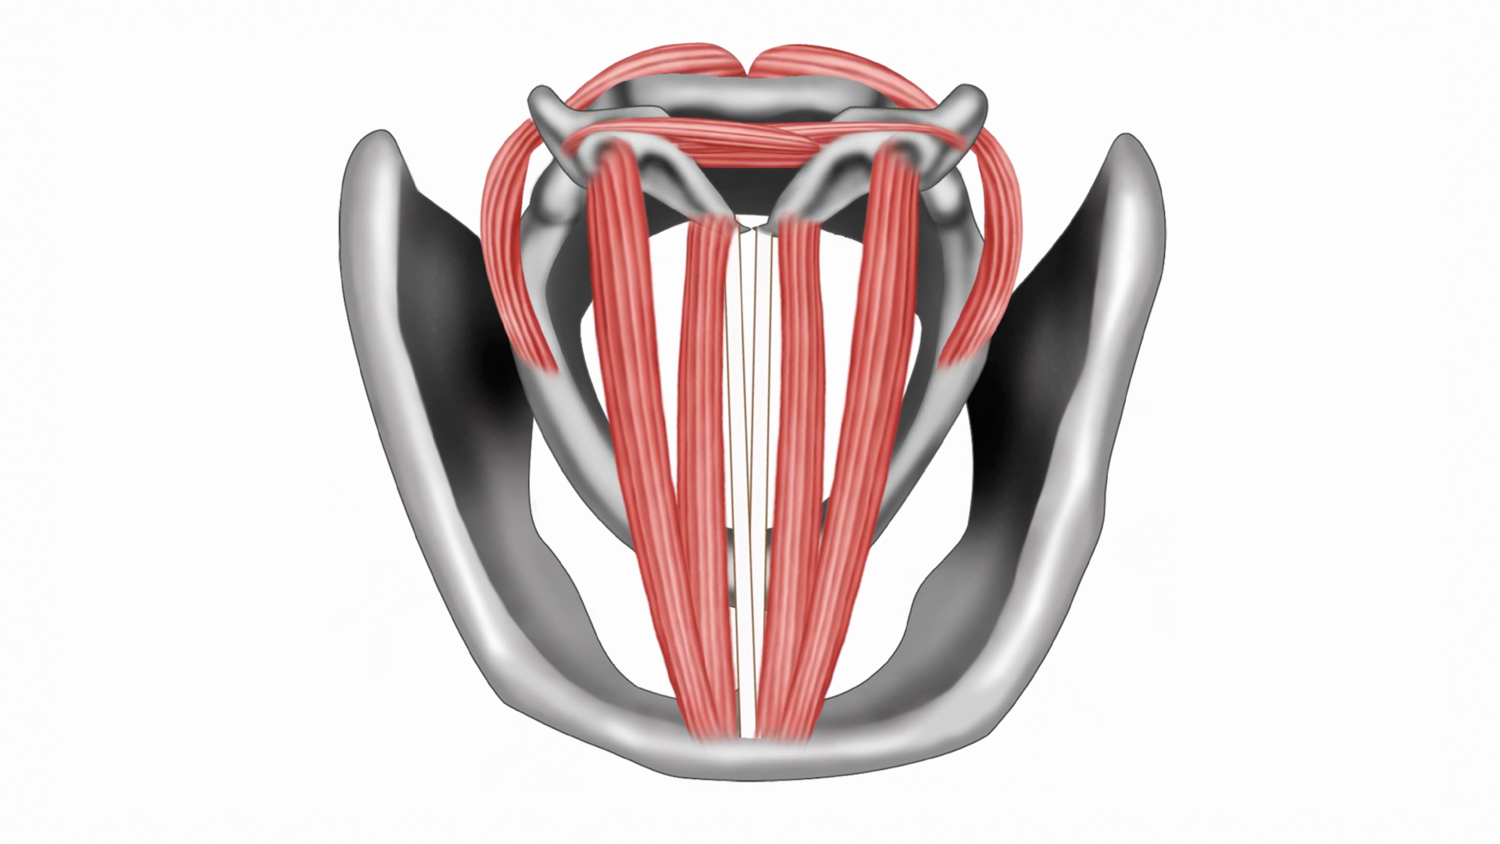

Module 5 - Larynx

In module 5, we dive into the action of the vocal folds. We examine the muscles that enable you to change pitch and regulate breath flow. You will learn about terms like chest, head, and mix. We will also discuss what the vocal folds are doing to produce each quality.